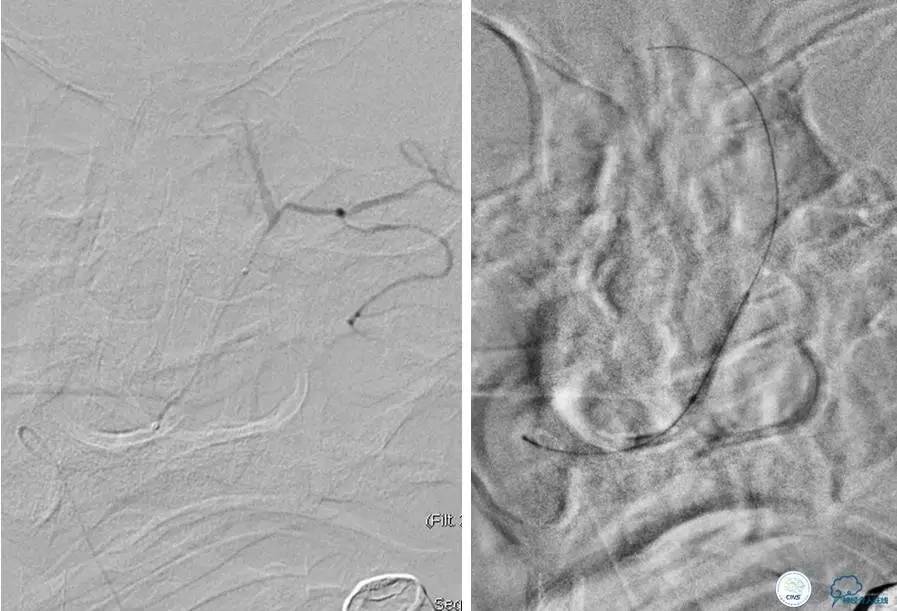

患者:49岁男性,左侧偏瘫1个月,药物治疗、康复训练效果不好,转我院,肌力0~1级。

core-clilnical明显不匹配,是介入开通的合适患者。

造影评价血管、判断闭塞段,微导丝小心穿过闭塞段,微导管造影,交换技术,球囊扩张,Enterprise支架。在后扩张时导丝刺破M3段血管,蛛网膜下腔出血(SAH)。

微导管进入破裂血管,栓塞弹簧圈1枚,出血停止,结束手术。继续双抗,术后2天肌力2级,神经功能恢复明显加快。

术后即刻和6天后CT,患者无明显临床症状。

半年后复查造影,无支架内再狭窄,可见弹簧圈,患者恢复至自己柱杖行走。